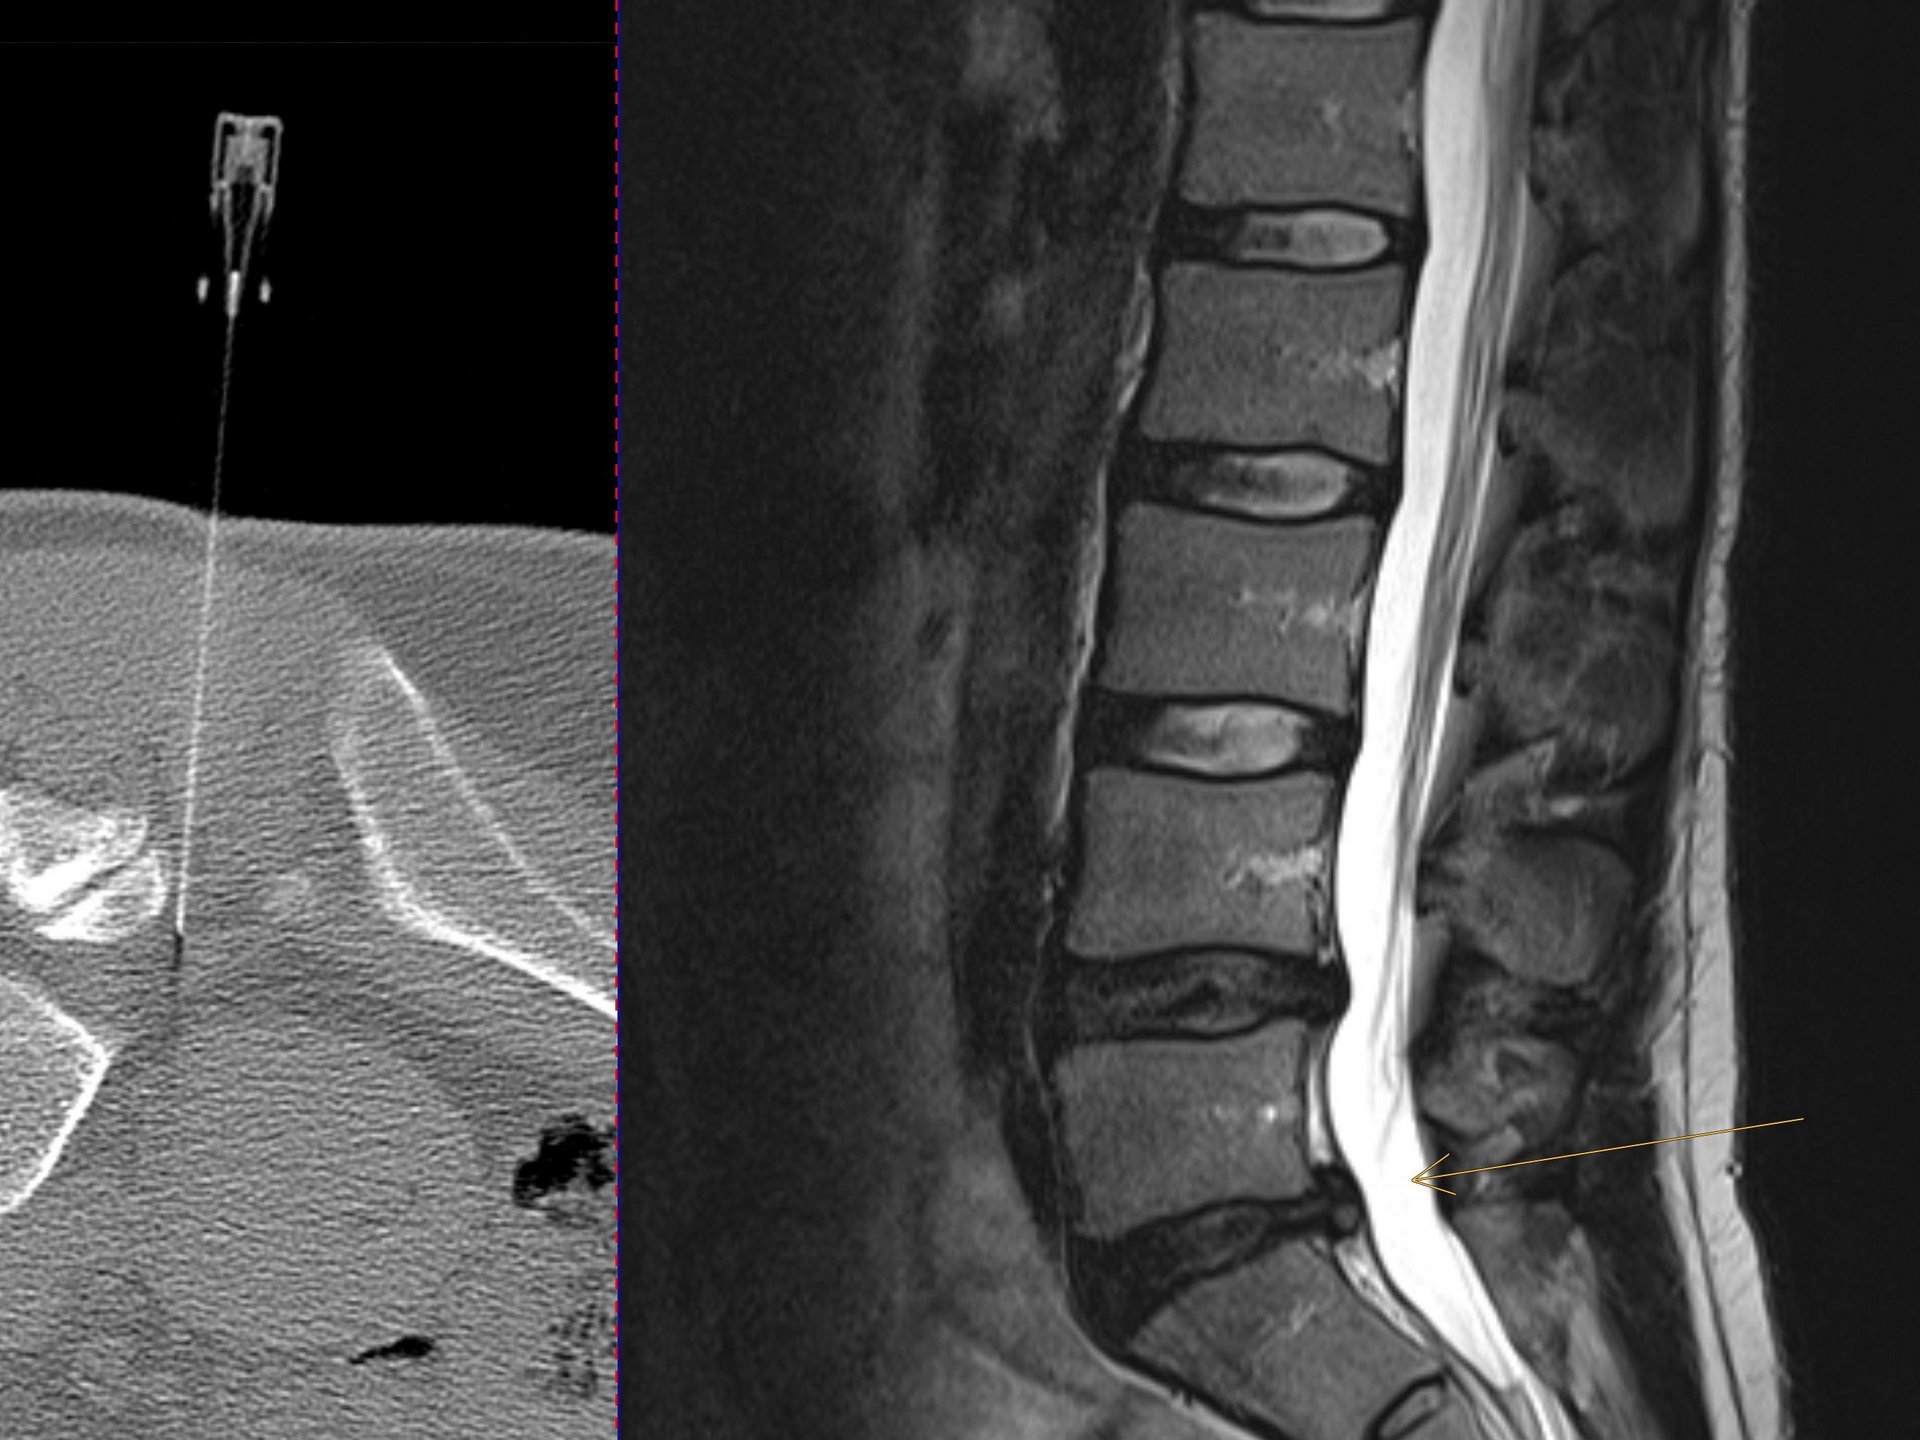

Die periradikuläre Therapie (PRT) ist das am häufigsten eingesetzte schmerztherapeutische Verfahren bei einem Bandscheibenvorfall aber auch anderen Rückenerkrankungen, bei dem unter CT-Kontrolle schmerzstillende Medikamente präzise an die schmerzende Nervenwurzel gespritzt werden. Hierbei kommen Kortikosteroide und langwirksame Lokalanästhetika zur Anwendung. Die Kortikosteroide führen zu einem Abschwellen der gereizten Nervenwurzel, die Lokalanästhetika reduzieren die lokale Schmerzausstrahlung. Durch das Abschwellen der Nervenwurzel besteht wieder relativ mehr Platz im Austrittsbereich des Nervs an der Wirbelsäule, so dass ein Bandscheibenvorfall nicht mehr die angrenzende Nervenwurzel reizen kann. Zudem wirken beide Medikamente entzündungshemmend. Durch den Einsatz von Depotmedikamenten wird hierbei ein Langzeiteffekt erzielt.Einsatzgebiete: